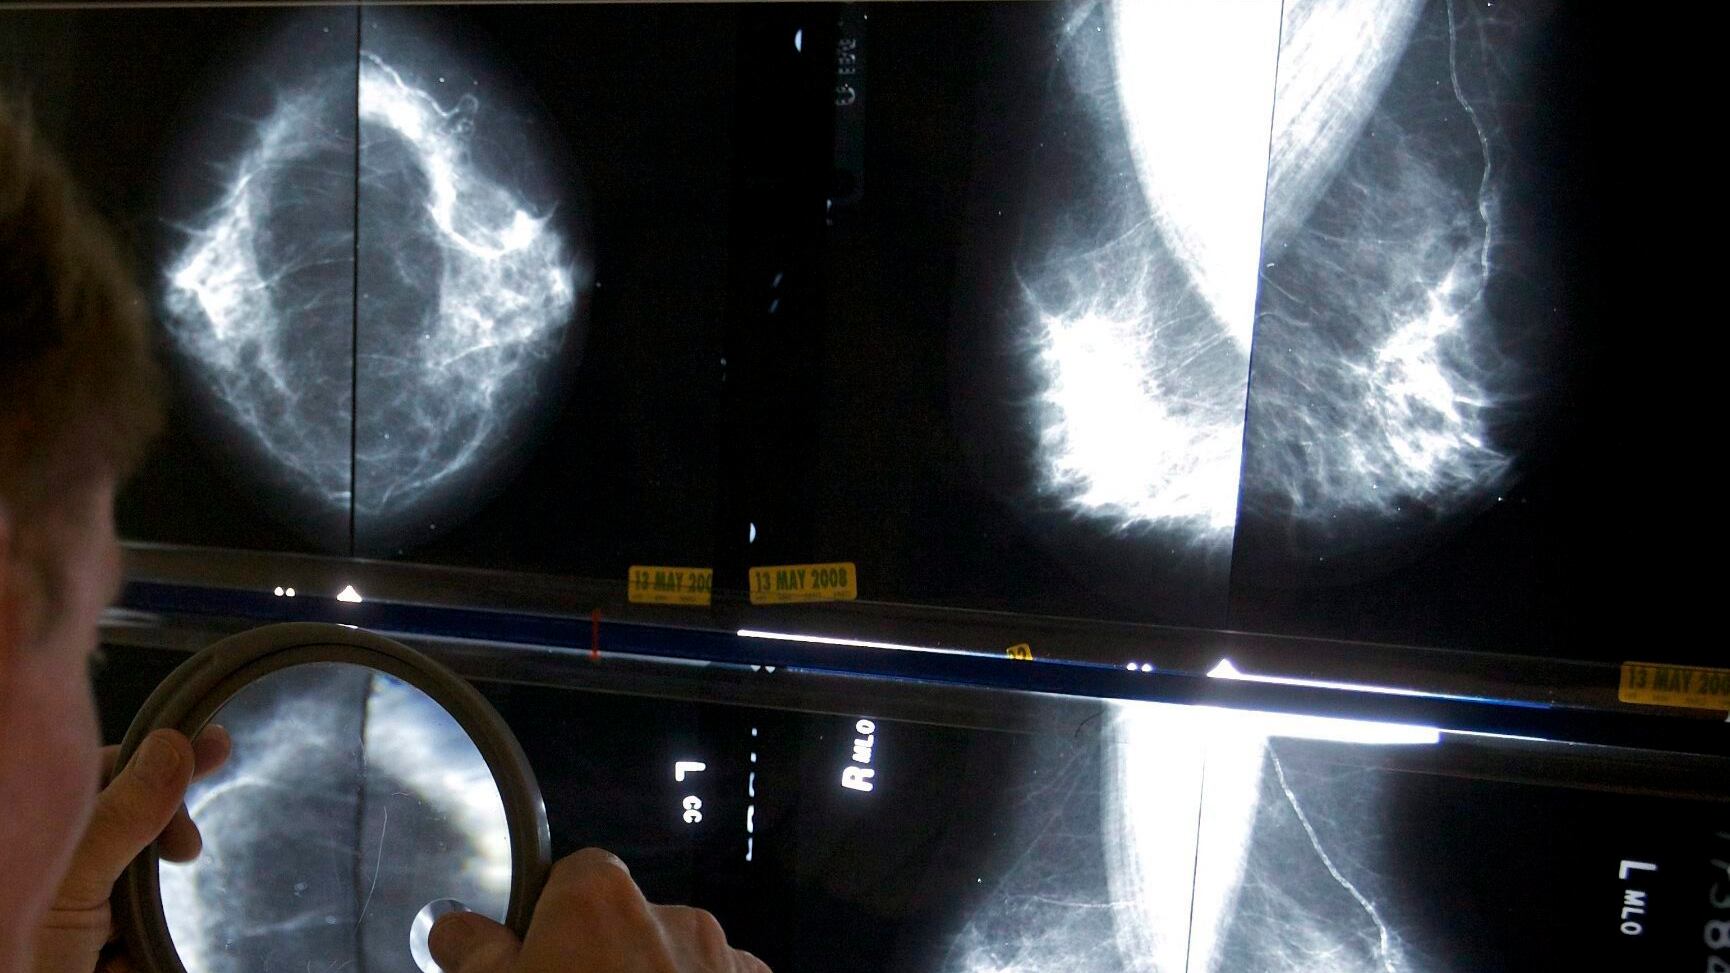

A new study has found that Black women face up to 70 per cent higher death rates from breast cancer compared to white women, prompting medical experts and advocates to call for increased risk-based screening in Canada.

The study analyzed breast cancer incidence, age at diagnosis, stage, subtype, and death in Canadian Black women by different ancestry groups.

It found that Black women of Caribbean origins had a 70 per cent higher death rate than white women at ages 40 to 49 and a 42 per per cent higher death rate between ages 50 to 59. The study also found that Black women died of breast cancer younger than white women: the average age of death for Black women was 53 to 66, compared to 71 for white women.